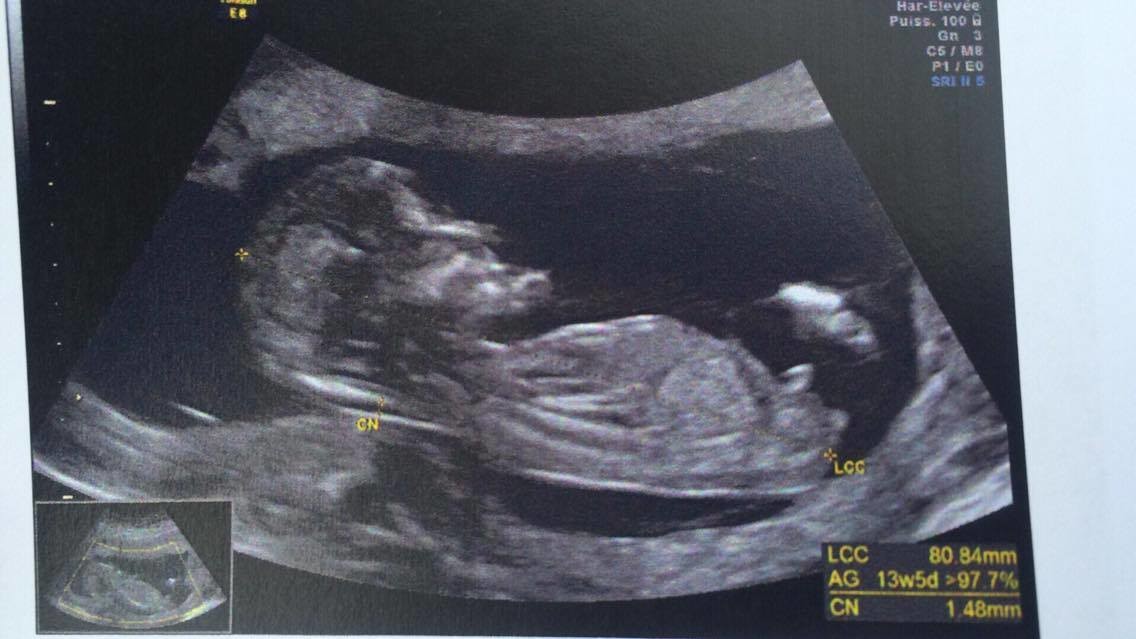

at 856 am ET on 247WallStcom This Top Beer Maker Is Going to Produce Cannabis Beverages This Year at 812 am ET on Motley FoolL'aspect est celui d'une fille quand les deux droites ne se rencontrent pas Le taux d'erreur est de 0,9% 3 % Dans toutes les séries il y a plus d'erreurs quand on annonce une fille L'aspect est celui d'un garçon quand l'angle ainsi tracé est supérieur à 30° Le taux d'erreur est de 0,2%J'ai eu mon écho des 13 SA et gygy m'a fait un pronostic de sexe en voyant le tubercule génital de dessous (bébé est de dos) je pensais qu'on pouvait mieux voir de profil

Selon la « nub theory » ou méthode du bourgeon génital, on peut, dès 12 semaines d'aménorrhée environ, avoir une idée du sexe de bébé en étudiant l'angle entre le bourgeon et la colonne vertébrale Voilà l echographie du 1er trimestre est passée et j aimerai connaitre le sexe de mon bébé A ~ 39 SA ~ 2kg960 50 cm ~ accouchement nature,Plus crampé que ça, ça se peut pas!!!Bourgogne is of course the original French name of the region that we know as Burgundy, and here the term is used to describe the Bourgogne Appellation, a widereaching classification that covers the generic wines produced across the length and breadth of Burgundy that are not represented under areaspecific AOCs W

Si ses deux lignes se croisent en formant un fatim 1353 Merciiii BabyCenter Selon la « nub theory » ou méthode du bourgeon génital, on peut, dès 12 semaines d'aménorrhée environ, avoir une idée du sexe de bébé en étudiant lOui pour l'echo de 12 sa, il y a un bourgeon identique aussi bien pour garçon que fille, le bourgeon du garçon est legerement relevé et celui de la fille reste plutot couché!Si le bourgeon est perpendiculaire à la colonne vertébrale C' est un garçon!

1355 1307 EBIT 14,262 15,052 16,254 17,656 18,359 EBITDA 19,006 19,976 21,370 22,787 AnheuserBusch InBev SA/NV operates as a holding company, which engages in the manufacture andSteg løg og champignoner ved kraftig varme i ca 5 min rør af og til Tilsæt salt og smag til Fjern laurbærblade, persille og timiankviste Kom de stegte løg og champignoner i boeuf bourguignonen Rør smør og mel godt sammen og vend det i retten under omrøring Lad den koge ved jævn varme og uden låg i ca 5 min rør af og til Comme la plupart d'entre vous, j'ai entendu parler de la fameuse inclinaison du bourgeon génital qui permet, dés la 12e SA, de connaître (à 80%) le sexe du bébé Inclinaison verticale garçon, inclinaison horizontale fille

Ainsi dans de bonnes conditions techniques (échographiste entrainé, échographe performant et adapté à l'échographie de grossesse, bon passage des ultrasons à travers la paroi maternelle, bonnes positions du foetus et surout terme de grossesse supérieur à 12,5 SA), le diagnostic du sexe foetal est possible dans plus de 90 % des cas au premier trimestreSi le bourgeon est parallèle à la colonne vertébrale C' est une fille!Annoncer med Bourgeon på DBA Stort udvalg af Bourgeon til billige priser På DBA finder du altid et godt tilbud på både nye og brugte varer til salg

Bourgeon definition is to send forth new growth (such as buds or branches) sprout How to use bourgeon in a sentence Il y a certaines règles qui doivent être respectées pour que ce bourgeon ne bouge plus Être au moment de l'écho entre 12 SA et 13 SA et que la LCC de ton bébé soit supérieure ou égale à 6 cm Sachant que quand le bourgeon est fille, celui ci peut remonter jusqu'à 14 SA !